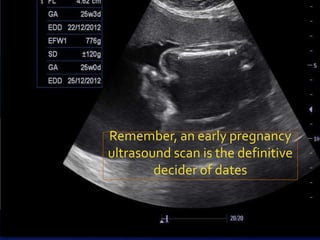

That an early pregnancy ultrasound (if

done), confirmed the dates

Remember, an early pregnancy

ultrasound scan is the definitive

decider of dates

In all cases,always begin by Dates confirming the dates Be absolutely positive The mother remembers the exact LMP (1st day) The periods have been regular The onset of pregnancy symptoms & quickening correspond to the dates That an early pregnancy ultrasound (if done), confirmed the dates Subsequent antenatal check ups have noted previous corresponding growth of

Remember, an earlypregnancy ultrasound scan is the definitive decider of dates